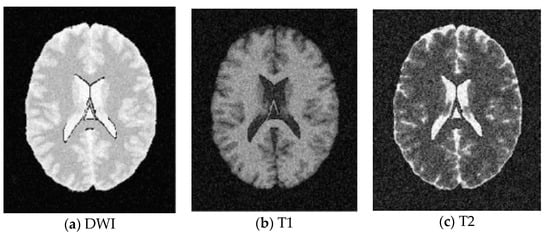

SBD: The database has DWI, T1 and T2 images of size 181 × 217 pixels. In our experiments, the classification results were quantified based on the ground truth of SBD. We added Rician noise to the analog image. In our experiments, the SNR (signal to noise ratio) values were set to 10 dB, 5 dB, 15 dB, and 20 dB, respectively. Shown in Figure 7, Figure 8, Figure 9 and Figure 10 are SBD images.

Figure 8. SBD Images with SNR = 5 dB.

Entropy 20 00964 g008